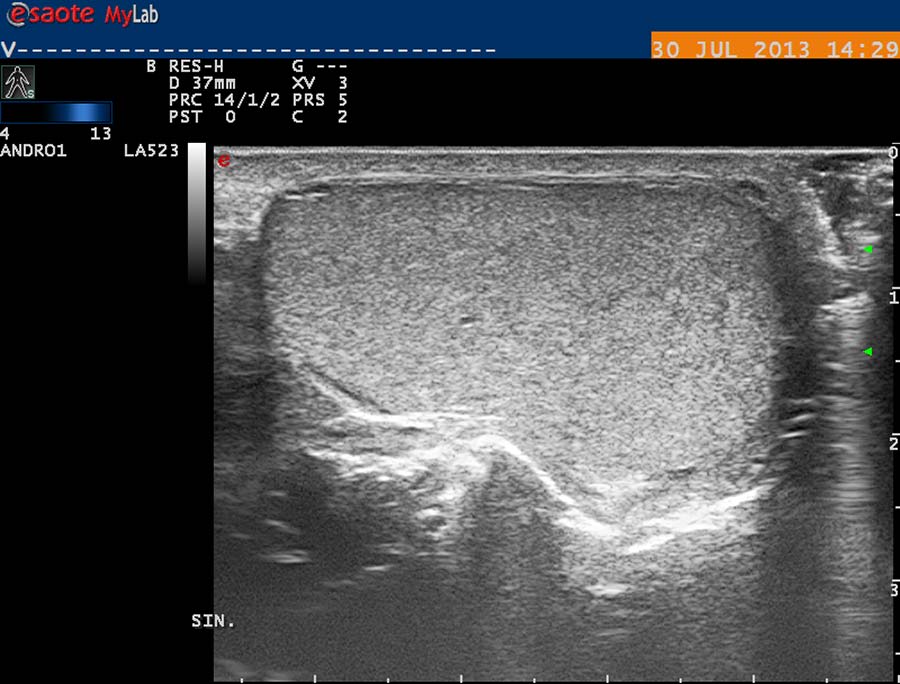

USG diagnostika vyžaduje odpovídající vybavení (obr. 12), zkušenosti a dostatek času. Vyšetření USG provádíme po termografickém vyšetření, na lůžku vyhřívaném na 30 st. Celsia, ultrasonografický gel zahříváme ve vodní lázni na teplotu 35 stupňů. Chladová kontrakce musculus cremaster vede k falešně negativním nálezům. Základní projekcí je koronární sken varlete (obr. 14) následovaný volumometrií ve dvou rovinách (obr. 15). Již na těchto skenech varlete je patrné rozšíření intratestikulárních cév, lépe je však viditelné při harmonickém („tissue enhancement imaging – TEI“) zobrazení (obr. 16, 17), a při barevném Dopplerovském zobrazení (Power Doppler) s TEI (obr. 18) s měřením šíře stěny a lumen žíly. Objemné dilatované žíly pampiniformního plexu jsou velmi dobře patrné na kolorizovaném TEI zobrazení (obr. 19), kde je možné zachytit pohyb venózní krve v souvislosti s dechem, intraabdominálním (IAP) a intrathorakálním tlakem. Informaci o atrofizaci tkáně získáme ze záznamu deformace kontury tunica albuginea podložkou, kterou je měkká buničina vložená pod skrotum (obr. 20, obr. 21 s volumometrií). Triplexní Dopplerovský záznam umožní hodnotit délku žilního refluxu a rychlost proudu refluktující krve v inspiriu, reflux při zvýšení intraabdominálního tlaku (obr. 22,23). Duplexní Dopplerovský záznam při harmonickém zobrazení s kolorizací zachycuje senzitivně změnu rychlosti proudění při refluxu v inspiriu s navazujícím zvýšením rychlosti při IAP (obr 25). Významná je možnost zachycení refluxu při klidném dýchání (respirační reflux, obr. 26).

obr. 16

obr. 17